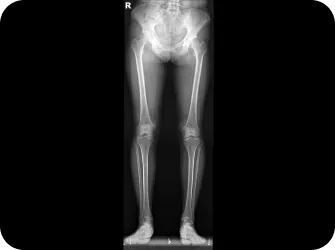

다리 틀어짐

휜다리 / 오다리 / 엑스다리

전신 엑스레이 검사

턱, 어깨 높이, 골반 틀어짐, 부정렬

다리길이 엑스레이 검사